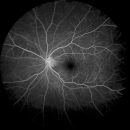

Die Fluoreszenzangiographie dient der Untersuchung der Gefäße am Augenhintergrund. Dabei wird ein Kontrastmittel in eine Armvene gespritzt, das nach ca. 30 Sekunden die Blutgefäße im Auge erreicht. Mit einer speziellen Kamera wird der Augenhintergrund fotografiert.

Die Auswertung der Aufnahmen ermöglicht eine genaue Diagnose der Netzhaut. Durchblutungsstörungen, Gefäßverschlüsse und andere krankhafte Veränderungen können festgestellt werden. Deshalb ist diese Untersuchung bei einer Makuladegeneration und bei Diabetikern besonders wichtig.